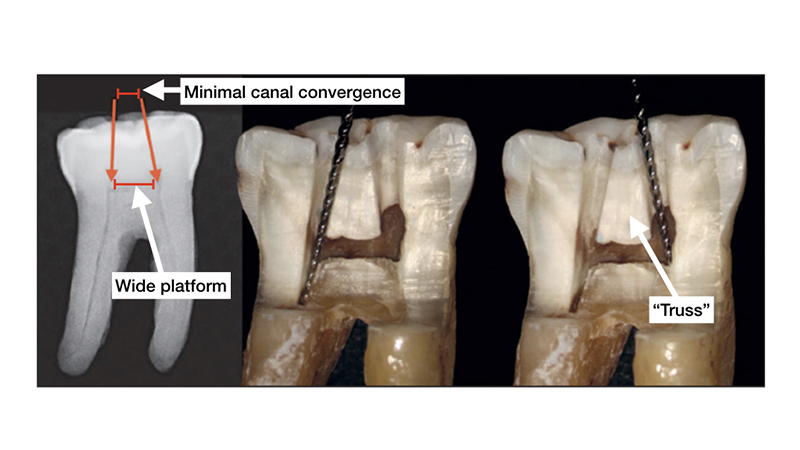

Trends Towards Conservative Endodontic Treatment

Introduction Consider a new patient who has come to a dental office and undergoes a screening examination. A quick look at any missing teeth may prompt a dentist to ask, why were these teeth lost? While patient responses may be vague, the answer often involves fractured endodontically treated teeth (ETT). For the most part, teeth … Read more